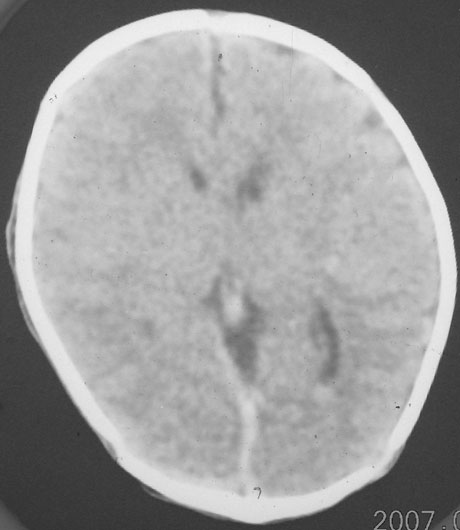

以下是引用rjg199343在2007-1-24 23:08:00的发言:[br]纵裂池、小脑幕、双侧脑室内高密度影,符合脑室、蛛网膜下腔出血。